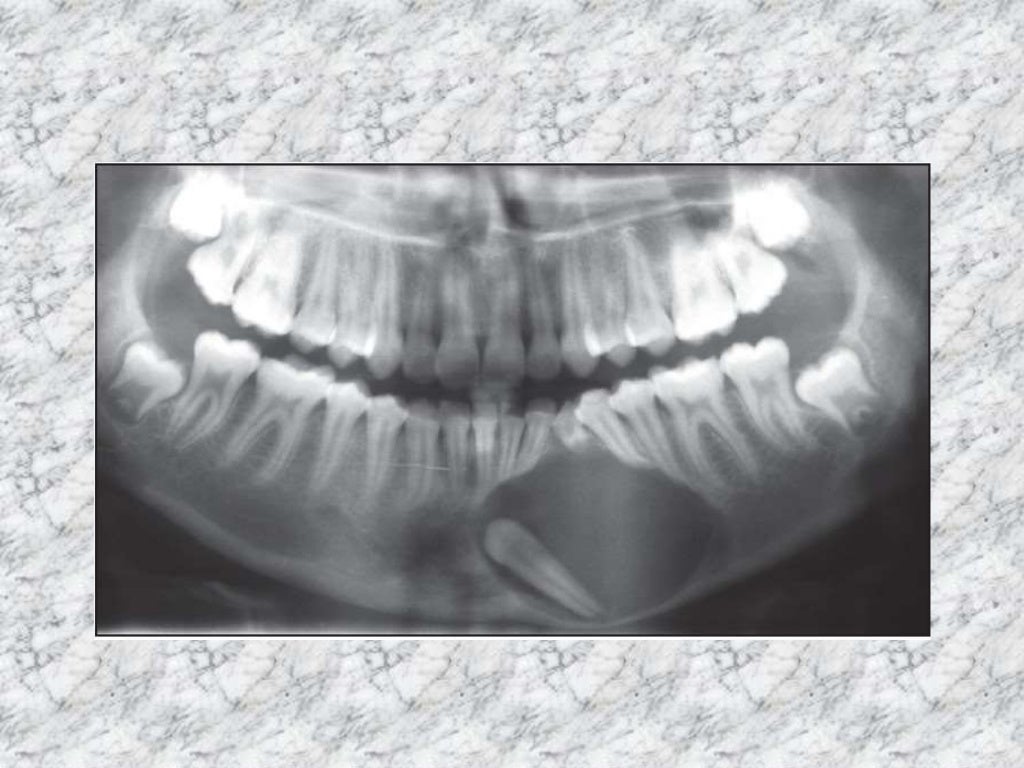

Panoramic Radiopacities Radiodontics Most Radiopaque Nonodontogenic radiolucencies tend to be. your patient points to a portion of the tooth that is the most radiopaque and wants to know what it is. The radiopacity values of gradia direct loflo, dentin and estelite flow q were close to that of 1 mm al. periapical radiolucencies are most commonly odontogenic. What is the most radiopaque. . Most Radiopaque.